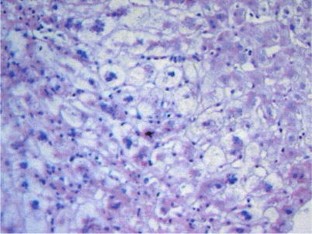

(a) The peak area ratios and altitudes of PME and PDE in biliary duct stricture group and chronic rejection group were higher than those of healthy volunteer group and normal graft function group. Patients with chronic rejection had significant differences in the peak area ratios of PME: β-ATP (P < 0.05) and PDE: β-ATP (P < 0.05) and in the altitudes of PME: β-ATP (P < 0.05) as compared with the other groups. (b) The ratios of β-ATP/Pi decreased in biliary duct stricture group, while they increased in chronic rejection group. There was no difference between the four groups. There were similar changes in the ratios of PME/Pi, but there was significant difference between the chronic rejection group and the other three groups. (c) pH values increased in biliary duct stricture group and chronic rejection group, though the difference was not significant with the healthy control group. (d) Histological specimens showed focal loss of hepatocytes, degeneration, and hepatocytic atrophy.